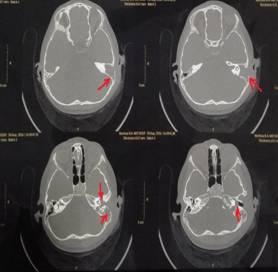

該患兒既往無中耳炎及耳流膿病史,僅表現(xiàn)為1個月前耳后稍有紅腫、疼痛,在當(dāng)?shù)蒯t(yī)院曾被診斷為“蚊蟲咬傷”所致,家長也未引起足夠的重視。近半月來,患兒耳后紅腫疼痛加重,遂到我市某三甲醫(yī)院就診,行高分辨率中耳乳突CT,發(fā)現(xiàn)側(cè)顱底、中耳乳突腔巨大新生物占位,乳突骨皮質(zhì)破壞吸收,并可疑耳后骨膜下膿腫形成。病情若進(jìn)一步發(fā)展,膽脂瘤破壞顱底骨質(zhì),將極有可能并發(fā)腦膜炎、腦膿腫,甚至出現(xiàn)敗血癥、腦疝等,危及生命。

1.術(shù)前耳后紅腫 2.術(shù)前CT1